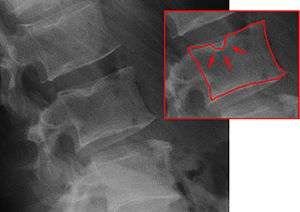

| X-ray image of Schmorl's nodes in the lumbar spine | |

Schmorl's nodes or Schmorl's nodules are protrusions of the nucleus pulposus of the intervertebral disc through the vertebral body endplate and into the adjacent vertebra.[1]

Schmorl's nodes can be detected with x-ray, although they can be imaged better by CT or MRI. They are considered to be vertical disc herniations through the cartilaginous vertebral body endplates. Schmorl's nodes can sometimes be seen radiographically, however they are more often seen on MRI, even when not visible on plain film x-ray. They may or may not be symptomatic, and their etiological significance for back pain is controversial. In a study in Spine by Hamanishi, et al., Schmorl's nodes were observed on MRI in 19% of 400 patients with back pain, and in only 9% of an asymptomatic control group. The authors concluded that Schmorl's nodes are areas of "vertical disc herniation" through areas of weakness in the endplate.